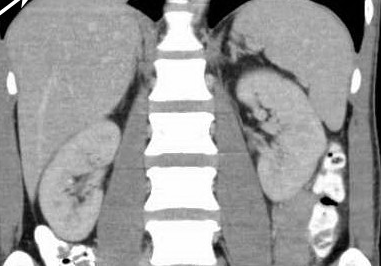

Renal oncocytoma with the characteristic central stellate scar of the neoplasm (Courtesy Dr. V. Penopoulos)